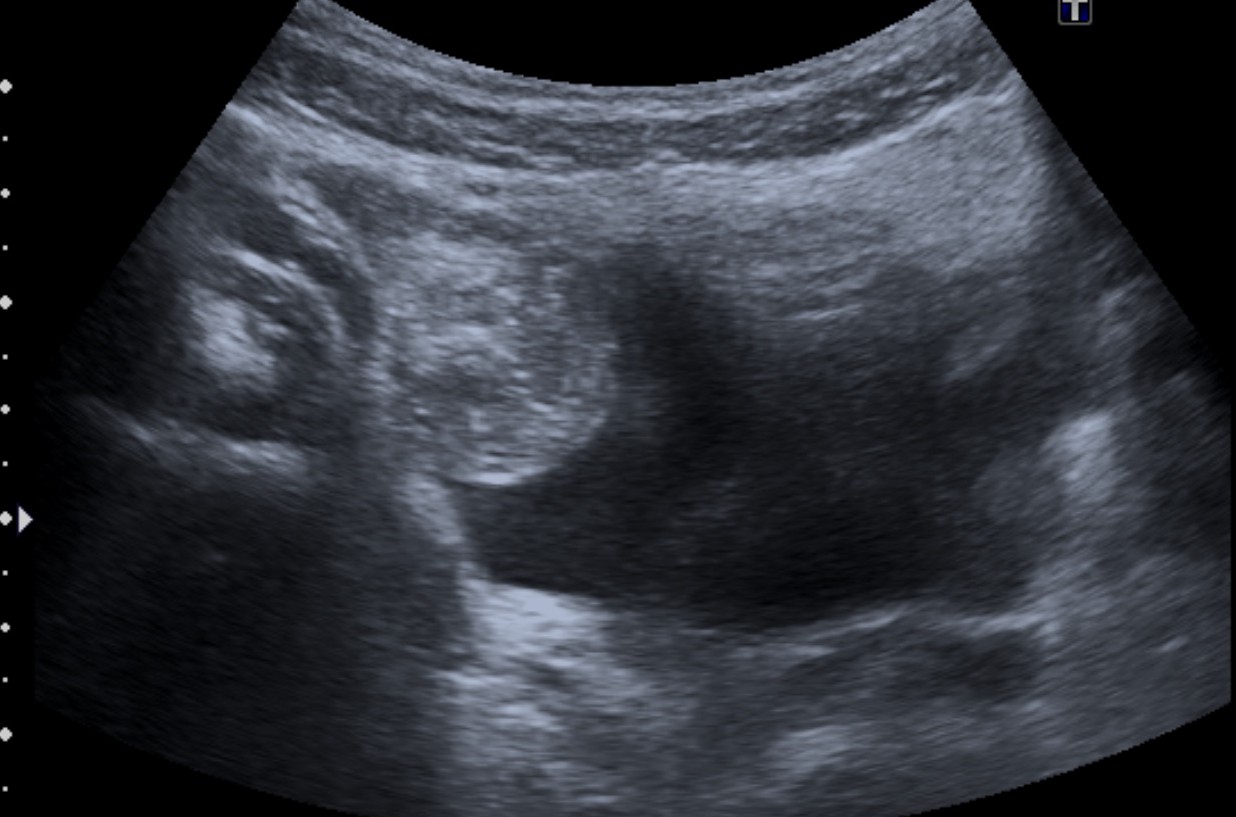

Se realiza ecografía de abdomen. Se observa:

El paciente presenta dolor, anemia marcada y clínica de obstrucción intestinal, lo cual puede ser debido a una invaginación intesinal ileoileal (aunque el niño tiene ya 9 años) o probablemente a un divertículo de Meckel complicado que puede haber producido una intususpección.

En la evaluación ecográfica se puede identificarse una estructura tubular que termina en saco ciego con contenido líquido, en el borde antimesentérico del íleon terminal,

localizada a nivel abdominal en cuadrante inferior derecho. Estos hallazgos han provocado que se diagnostiquen erróneamente como apendicitis cuadro de diverticulitis de Meckel, sin bien la actitud terpéutica (que suele ser la cirugía) no varía.

Puede observarse también como una estructura quística con paredes que recuerdan asas intestinales: banda hiperecoica que correspondería a la mucosa y otra banda hipoecoica que correspondería a la muscular. Han sido confundidos con quístes de duplicación (los cuales tienen sin embargo márgenes más regulares). La señal Doppler color puede muestran hiperemia como signo de inflamación del diverticulo.

Recordar que pueden econtrarse enterolitos en el interior del divertículo e incluso gas, el cual puede confundirnos con un asa intestinal (usar transductores de alta frecuencia).